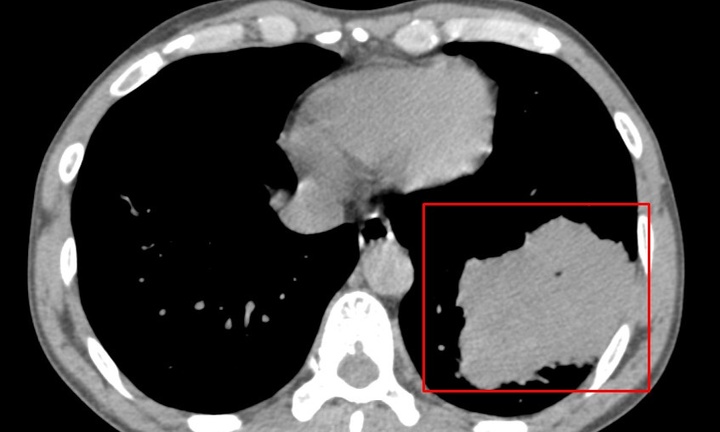

Người bệnh được chuyển đến trong tình trạng hết sức nguy kịch, có vết thương hở lớn vùng ngực trái dài gần 10cm do lưỡi cưa văng vào, thủng tim, sốc mất máu, ý thức lơ mơ, mạch và huyết áp không bắt được. Người nhà kể, bệnh nhân bị mảnh lưỡi cưa gãy bắn vào ngực trong lúc đang vận hành máy cưa.

Ekip các bác sĩ nhanh chóng mở ngực, giải phóng chèn ép tim. Kiểm tra tổn thương thủng tim phát hiện khoang màng tim có vết rách 1cm, đứt động mạch vú trong. Bệnh nhân được khâu vết thương tim, lấy máu đông khoang màng phổi trái, thắt động mạch vú trong và truyền máu liên tục.

Vì vết thương động mạch khá phức tạp, tổn thương tim lớn nên người bệnh mất nhiều máu, trong quá trình phẫu thuật, các bác sĩ đã phải truyền 5 đơn vị máu cho bệnh nhân. Sau gần 2 tiếng phẫu thuật cấp cứu, bệnh nhân đã cầm được máu vết thương, huyết động ổn định, sức khỏe tiến triển khá tốt, các chỉ số sinh tồn trong giới hạn bình thường. Bệnh nhân đang tiếp tục được theo dõi và điều trị tại khoa Phẫu thuật Thần kinh – Lồng ngực.